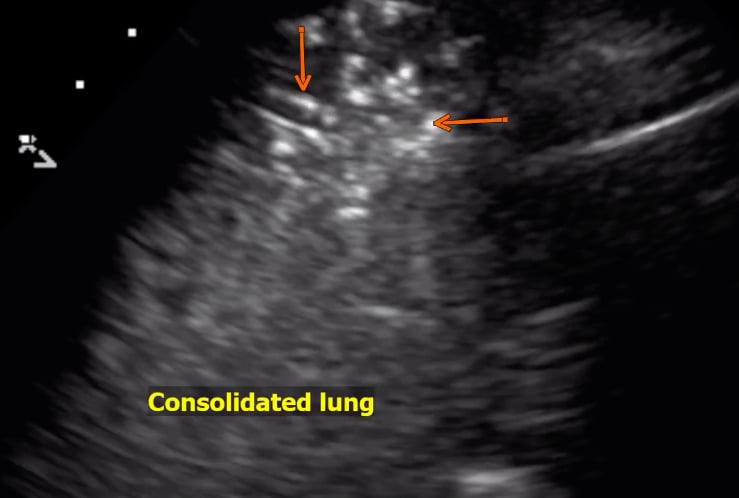

This photo gallery shows the variety of radiological presentations of COVID-19 (SARS-CoV-2) in medical imaging, including computed tomography (CT), radiograph X-rays, ultrasound, echocardiograms and magnetic resonance imaging (MRI). The radiology images show examples of typical COVID pneumonia in the lungs and the numerous complications the virus causes in the body in multiple organs, including the brain, kidneys, heart, abdomen and vascular system.

Ultrasound, especially hand-held ultrasound imaging devices, have become a primary imaging modality for novel coronavirus because of the ease to bag the device and sterilize it after use. CT and mobile X-ray systems are also used as front-line imaging systems for COVID-positive or suspected COVID patients.